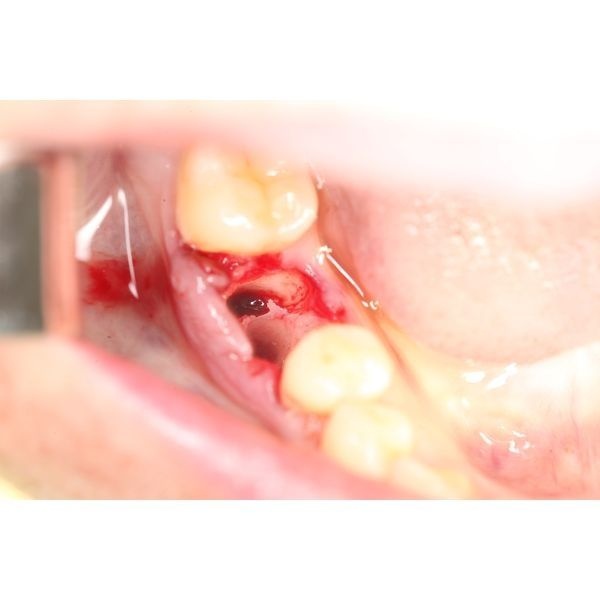

- сделали местную анестезию;

- удалили повреждённый зуб без корней;

- очистили лунку и остановили кровь;

- подготовили имплантационное ложе;